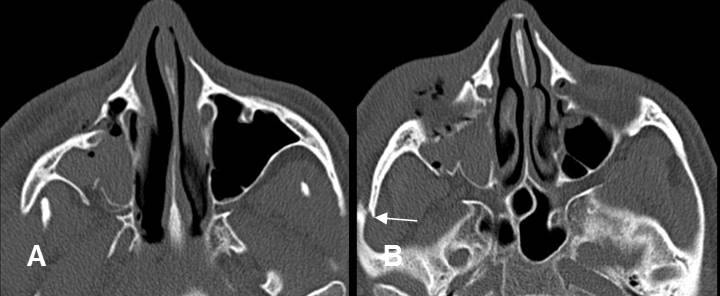

Fig 219. Láminas pterigoideas.

A: TAC axial y B: TAC reconstrucción coronal. Láminas pterigoideas normales.

Fig 220. Fractura de láminas pterigoideas.

A: TAC axial y B: TAC reconstrucción coronal. Fracturas de las láminas pterigoideas, hallazgo indispensable para hace el diagnóstico de fractura de Le Fort.